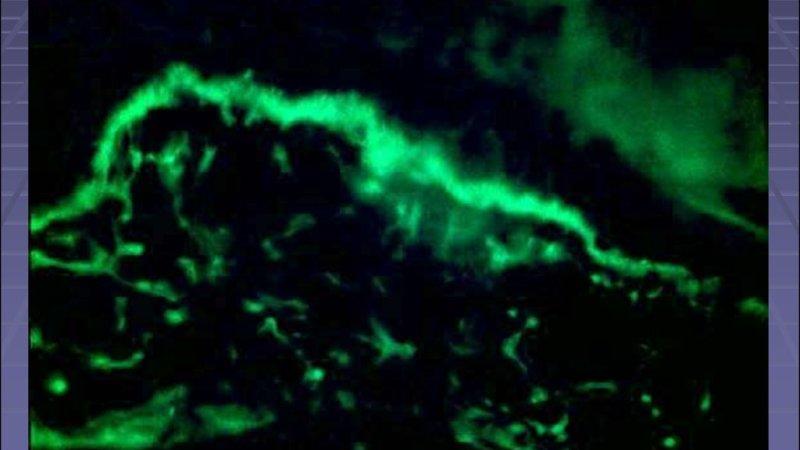

Обнаружение антител в крови осуществляется двумя основными методами. Первый из них — непрямая иммунофлуоресцентная микроскопия. При наличии антител они связываются с определёнными ядерными антигенами. В этом процессе используются флуоресцентные элементы, которые излучают свет в специфическом диапазоне. Благодаря микроскопии можно определить тип свечения.

Этот метод считается наиболее эффективным для выявления антинуклеарных антител и также известен как тест на волчаночные полосы.